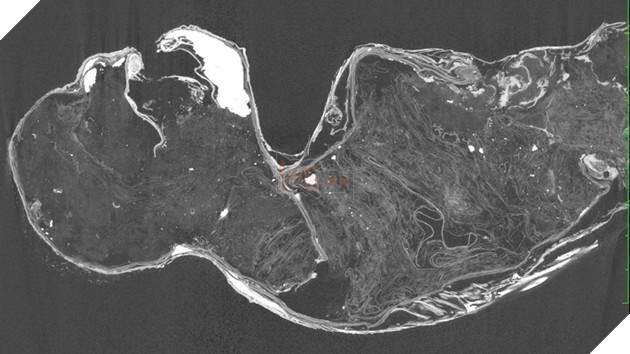

Năm ngoái, các nhà nghiên cứu từ Đại học Khoa học và Nghệ thuật Kurashiki đã tìm được xác ướp nàng tiên cá bí ẩn từ đền Enjuin và bắt đầu phân tích nó bằng nhiều kỹ thuật hiện đại, bao gồm chụp X-quang và CT (chụp cắt lớp vi tính), xác định niên đại bằng carbon phóng xạ, kính hiển vi điện tử và phân tích DNA.

Mẫu vật có kích thước 30,48 cm, với các bộ phận từ đầu đến thân là của một loài linh trưởng chưa phát triển và còn phần dưới thì là đuôi cá đã phân huỷ chỉ còn lại bộ xương. Bộ xương duy nhất còn lại nằm ở phần dưới của xác ướp và dường như thuộc về một con cá.

Vào ngày 7 tháng 2, nhóm nghiên cứu cuối cùng đã công bố phát hiện của mình, kết quả cho thấy phần thân đầu của mẫu vật không thuộc bất kỳ một loài linh trưởng nào. “Dựa trên phân tích của chúng tôi và lịch sử tạo ra xác ướp ở Nhật Bản, chúng tôi chỉ có thể kết luận rằng xác ướp nàng tiên cá có thể là do con người tạo ra”, Takafumi Kato, nhà sinh vật học cho biết. Để tóm lại, xác ướp này thực chất là búp bê với các bộ phận của cá hoàn toàn nhân tạo.

Kết quả cho thấy phần đầu của nàng tiên cá không thuộc về loài khỉ mà chủ yếu được làm từ vải, giấy và bông được giữ với nhau bằng các chốt kim loại chạy từ cổ xuống lưng. Nó cũng được sơn bằng hỗn hợp cát và than củi.

Tuy nhiên, phần thân được bao phủ bởi các bộ phận tước từ các động vật khác. Lông và da cá của động vật có vú, có thể là từ một con cá nóc, bao phủ các bộ phận của cánh tay, vai, cổ và má.

Hàm và răng của hiện vật cũng có khả năng được lấy từ một loài cá săn mồi và móng vuốt của nó được làm từ chất sừng, có nghĩa là chúng có thể đến từ một loài động vật có thật nhưng không thể xác định được. Phần đuôi của hiện vật thực sự là của một loài cá, có khả năng là một loài cá đù.

Các nhà nghiên cứu không thể xác định bất kỳ DNA hoàn chỉnh nào của linh vật này, nhưng việc xác định niên đại bằng carbon phóng xạ của vảy cho thấy chúng có thể có niên đại từ đầu những năm 1800.